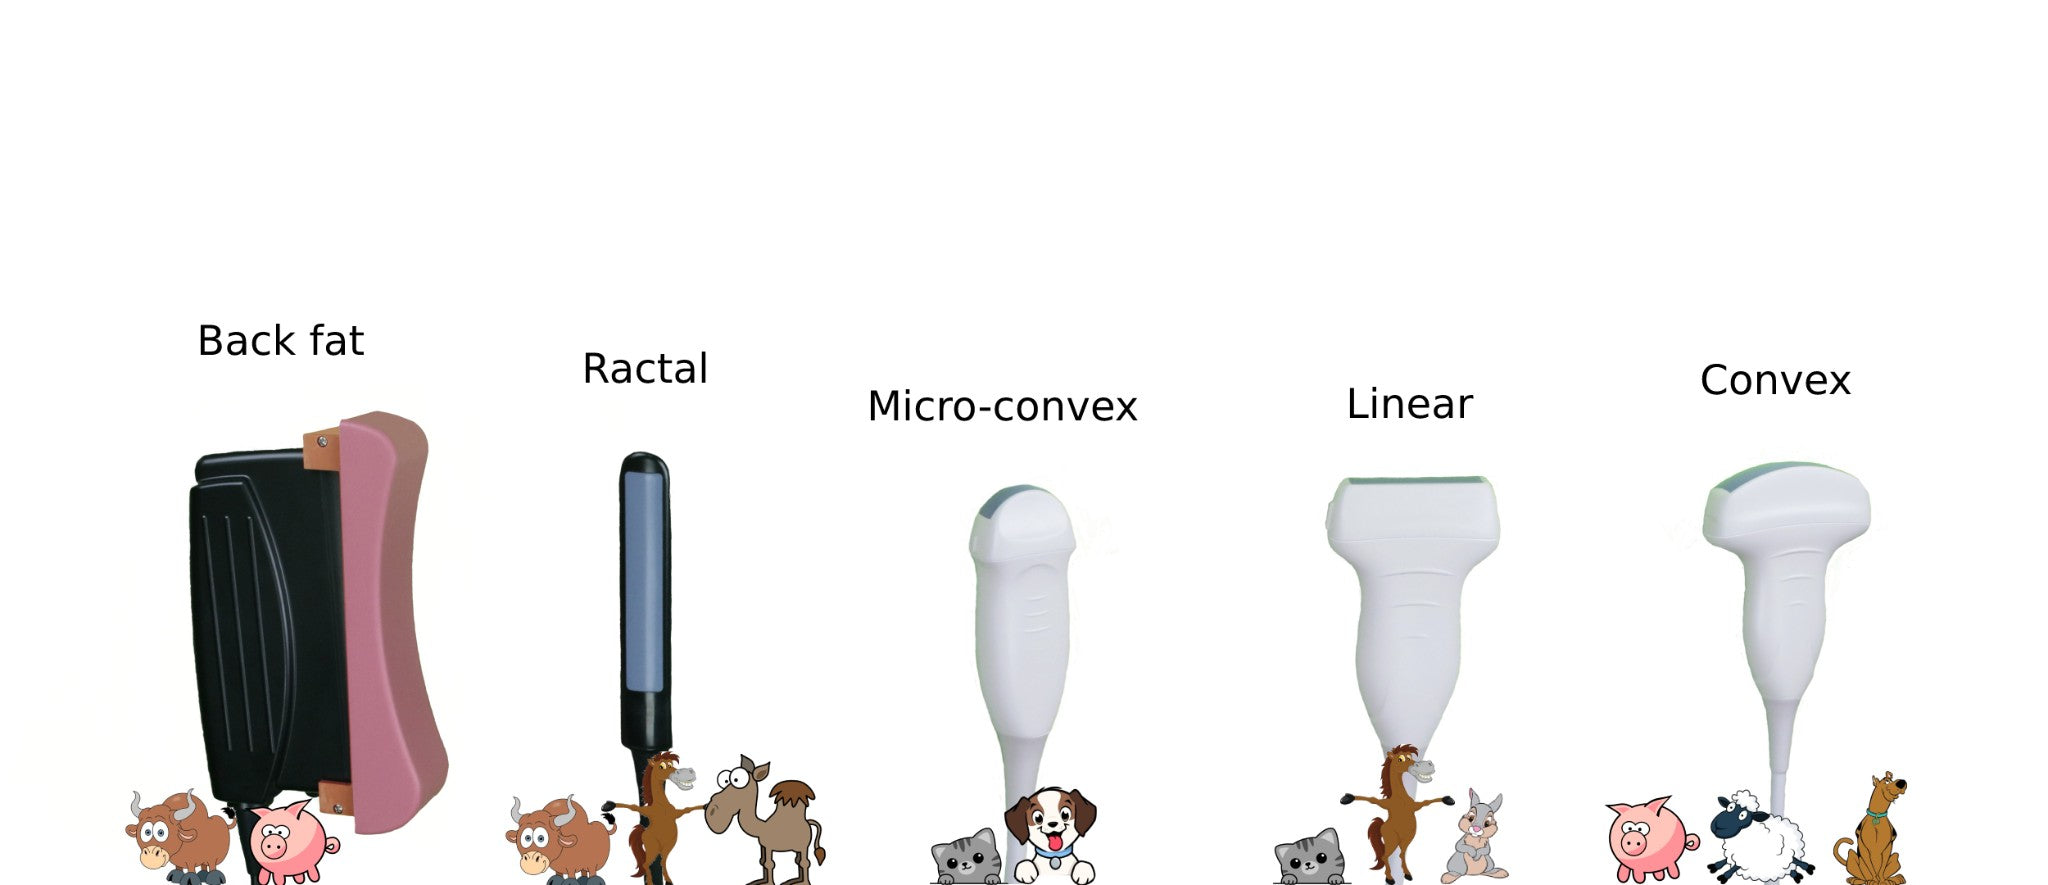

ECO-17Vet High end equine Ultrasound with Rectal Probe 4-12MHZ

6. The application range is very wide, including universities, research institutions on the rat heart and cranial, vascular blood flow, tumor detection, thrombus detection; experimental institutions on the rabbit blood vessel detection, real-time detection of blood flow, heart function, rabbit tumor detection; widely used in pet hospitals, pet clinics, pet stores, zoos, abdominal organs, superficial organs, heart, blood flow effects, etc.; fish The technology of checking fish roe/white/bubble/gonad, etc., for sturgeon egg size, fullness and egg quality control.

Probe connector ≥ 1